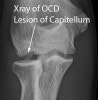

1. X-ray

1) Capitellum의 투과성(radioluceny), 희박성(rarefraction)

2) 관절면의 평편함과 불일치

3) 유리체 : 45º flexion AP, Oblique view

X-ray : 박리성 골연골염(Osteochondritis dissecans)